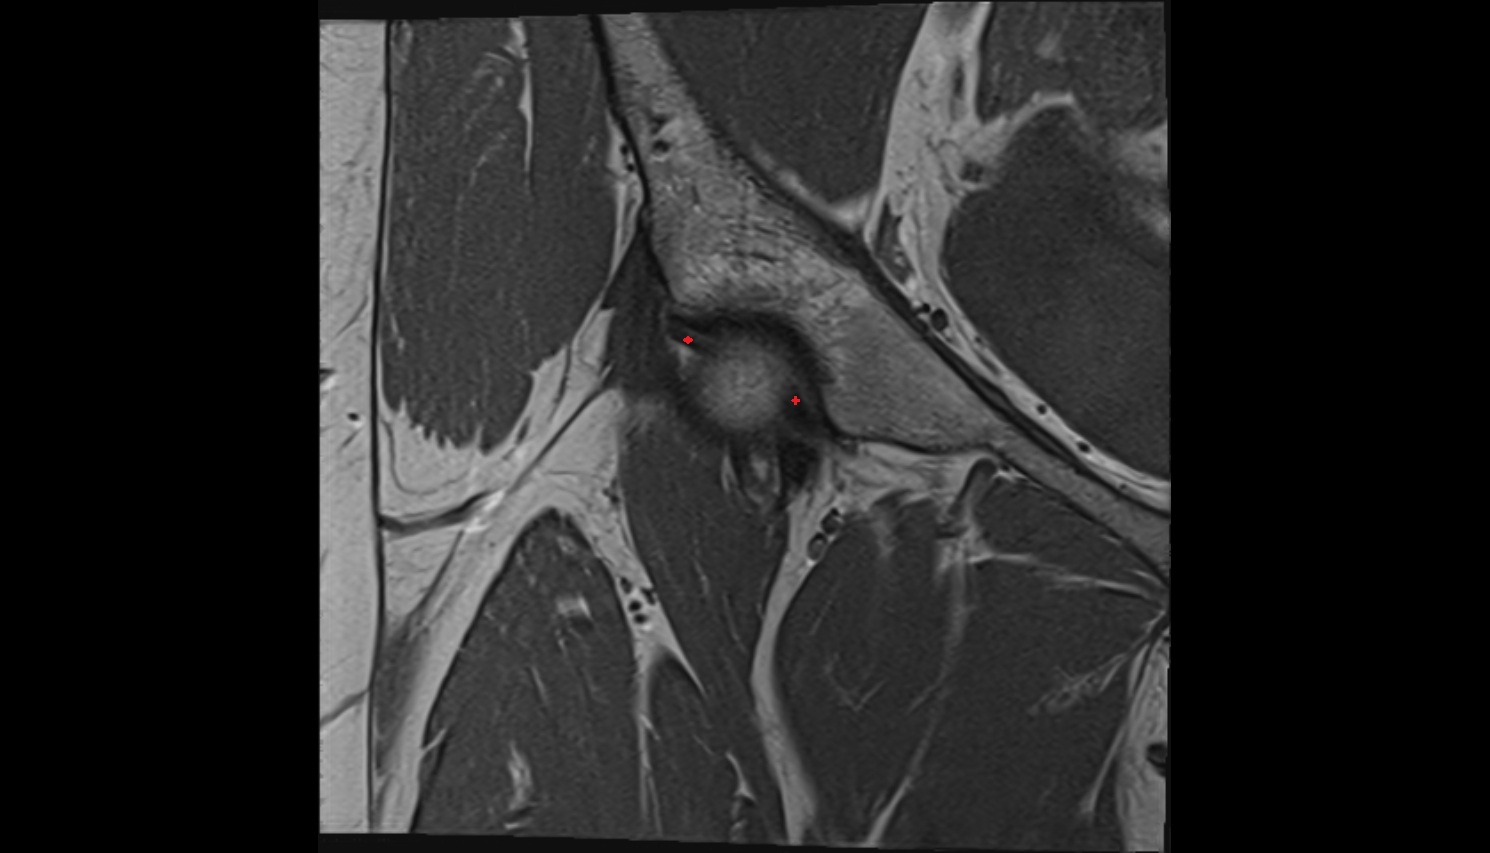

- Acetabular labrum

- Hip joint